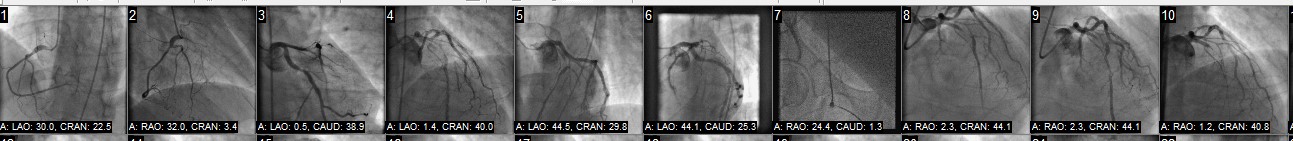

The angiograph strips below were taken during my stenting procedure. The radiation dose for an angiogram is mostly dependent on the time and energy used to obtain the results. Some procedures can be done in minutes others take longer. i.e. stenting. So depending on the procedure and size of the person of course the radiation doses for angiographs can range anywhere from 10-100 times more that a CTA in some cases. LATEST NEWS ON IMAGING, BIO ABSORD STENTS ETC. CAN BE FOUND here Shown below is photo of my main LAD before and directly after my stent, May28, 2013. Below photos where taken during the my stent procedure catheterization - angiography - angioplasty procedure Stents and Positive remodeling, Dr Srinivas explains. might be a good place to start especially if your Calcium score is high?

< CLICK ON PHOTO TO SEE THE SAME ARTERY PRE-CATH ON A CTA |

| The person that usually analyzing these types of diagnostic images is classified as a diagnostic radiologist, these types of doc's are usually bought up by money making diagnostic labs and cannot be found. I have had several cardiologists and not a one has every looked at an image or for that matter even wanted to. He or she will most likely at best just read his or her report, so asking questions about questionable images is hard pressed at best, such a shame ! |

Right Photos are my arteries and are links, yikes! What does artery disease look like on a CTA? A 2017 CTA photo of my arteries: The left photo unfortunately shows the current disease in the CFX artery. My recent radiological report from these photos mentions coronary artery disease only and depicts the stenosis within the artery as a percentage, mine is < 25% great, but this is only a guesstimate and can vary 10% 20% and up to 30% is my understanding. I have seen two cardiologists since with the radiological report and they both say great less than 25%, blockage while neither actually even bothered to look at the photo with the actually disease. I asked both doc's if they would like to see the photos and they both declined. The Stenosis reported in the above angio photo group (BEFORE / AFTER) at the time of the stent was reported as 40% 50% and 60% by angio cath and now by CTA they say < 25%, I am in the process of finding out by comparison if this is true, I will be comparing the 2013 CTA to the 2017 CTA. By observation I noticed the overall sublumenal disease show in photos has not seemed to change much if at all. I also learned that the angio photo guesstimates are just that and do not hold much weight as far a accuracy if at all, they appear to be visual guides with numbers attached by the surgeon and or helper at the time of the CATH, why bother except to sell more operations. So in 2013 my artery blockages were 40-50-60% determined by the angiogram now compared to a CTA they are less than 25%, yea right, wishful thinking for sure. The disease looks the same to me photos to be posted. Can't help thinking that they do many unnecessary by pass operations based on the CATH readings/photos which are at best only guesstimates in most cases. i.e. I recently had a friend diagnosed by CATH that he had 80% blockages is all four arteries and received an immediate quadruple by bass operation? When you go under you basically give them cart blanche to do what is necessary, the way I got around this was to get the CTA before the CATH, In my case I was pretty sure what was going to happen before the CATH.

|

In the above left photo white is calcified plaque, dark irregularities and raised areas are the disease itself . Of note: although the stenosis, narrowing is only 25% this give or take 10% -30%, yes. in most cases it is reported that the stable white plaque is not the soft vulnerable plaque that causes a heart attacks but instead its the dark areas of soft vulnerable plaque beneath the artery walls that tend to be the culprits, however they actually can occur anywhere at anytime. The idea is that through (positive remodeling) the plaque builds up pressure beneath the artery wall and finally when enough pressure or disease happens within, the area is subject to rupture. If the artery blockage us severe enough a heart attack can ensue. So passing all your basic yearly tests really don't mean a thing buddy, imaging is key! |